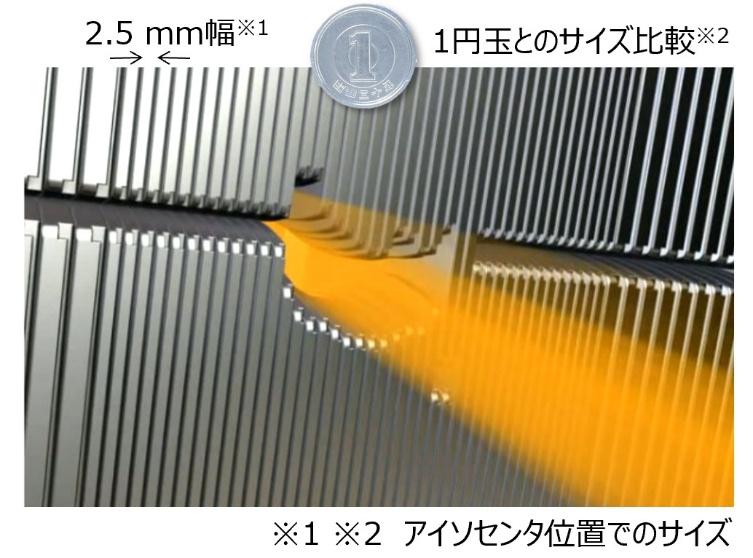

多分割コリメータ(HD120 MLC)

HD120 MLC(High-Definition Multi-Leaf Collimator)は、放射線の形状を細かく制御するための多分割コリメータです。腫瘍の形状に合わせた高精度な照射野の形成に寄与します。

コリメータ1枚あたりの幅はアイソセンタ(中心)で2.5 mmと非常に薄く、直径数 mm の転移性腫瘍に対してもピンポイントでの照射が可能です。